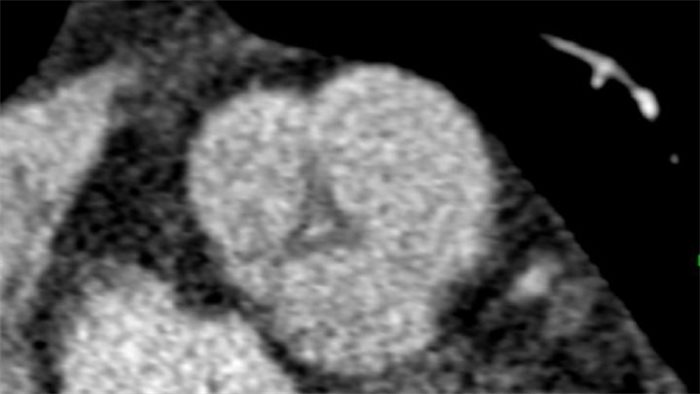

Cardiac CT scan - Thomas F Heston

NHS Lothian has written to 186 patients who have had a heart operation in the last six months warning that they may have picked up an infection during surgery.

The health board said it had written to all patients who have had a heart aortic valve replacement to advise them of a possible risk, after six patients had contracted “unusual infections”.